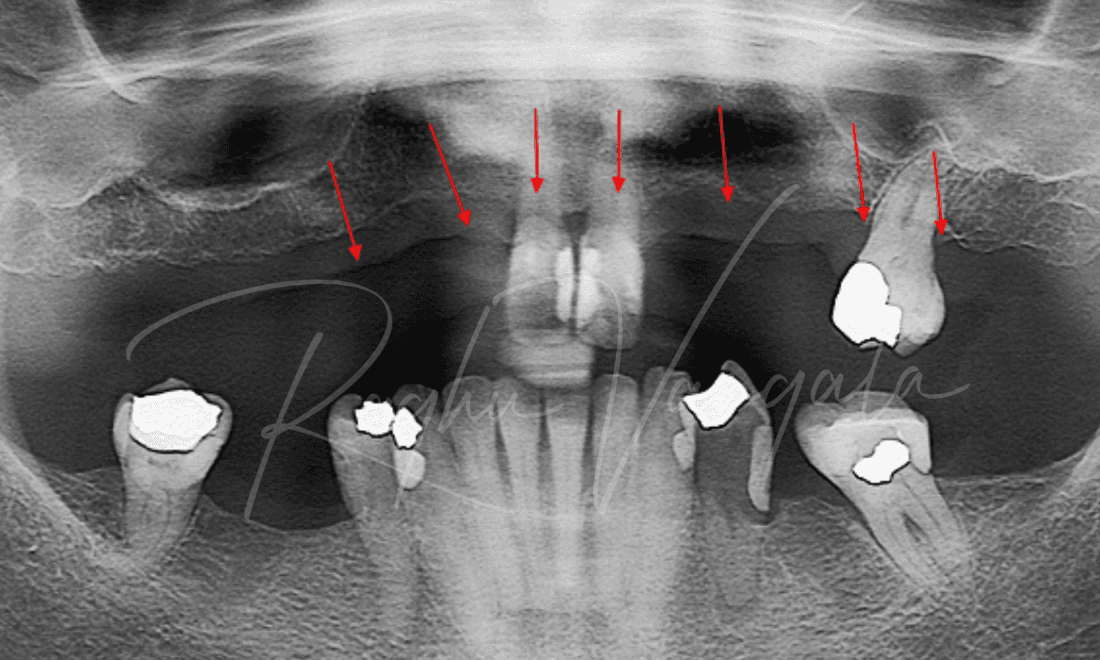

This lovely lady came to us wanting options to have a beautiful smile again. She had a partial upper plate and a few teeth left on her upper jaw. She wasn't a fan of her partial plate as it didn't feel right in her mouth. Her options for her upper teeth were to either get an upper denture or get implants and get a fixed denture. She decided to go with the permanent option, this consisted of getting her remaining upper teeth out and placing 5 implants. We then placed her upper denture a week later. She is very happy with the results and is now smiling like she was when she was younger.